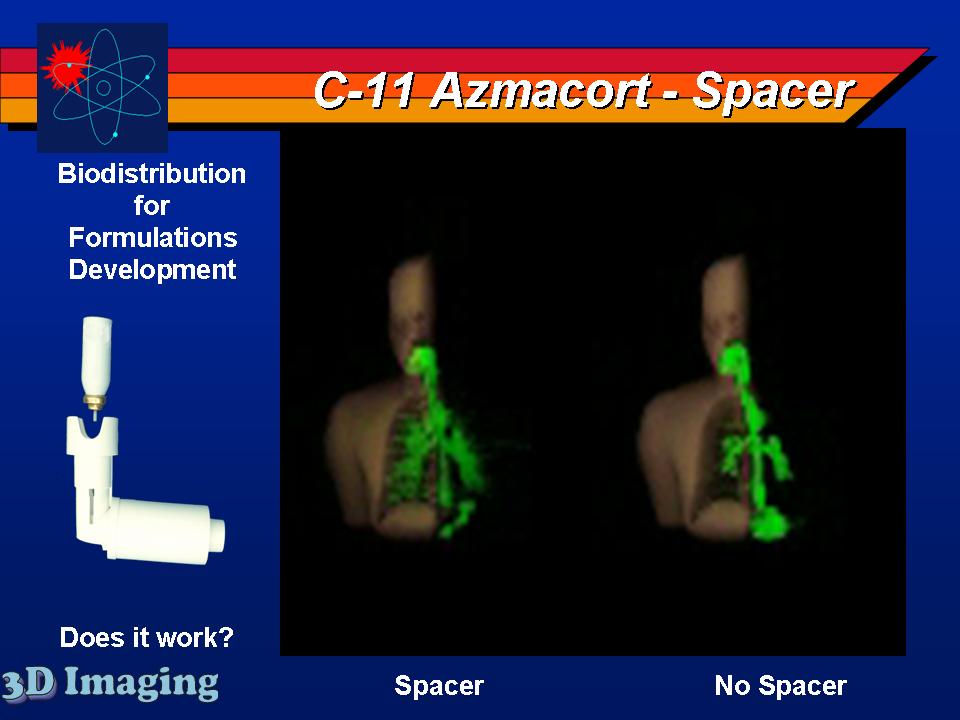

Several inhaled drug formulations were studied by radiolabeling the active ingredient (several different steriods) with C-11 or F-18, formulating that ingredient as the dosage form (different MDI, DPI, and nebulizer formulations), and performing quantitative PET studies of the regional biodistribution and kinetics.

Click on images to see additional examples, larger versions, and videos.